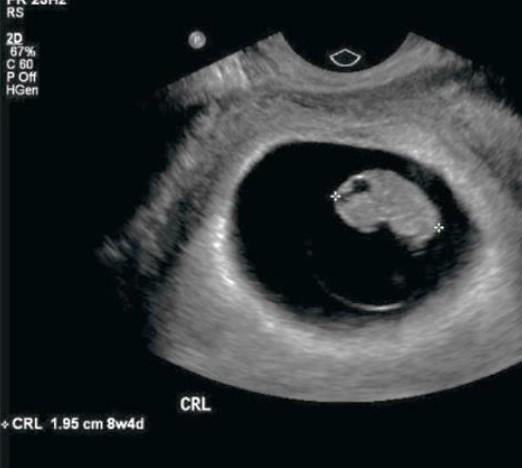

Paciente, na 8ª semana de gestação, procura atendimento após sangramento via vaginal. De acordo com a imagem a seguir, é correto afirmar que